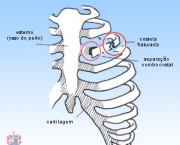

As dores da Costocondrite são causadas por uma inflamação da cartilagem que faz a ligação entre as costelas e osso do peito. Existem níveis dessa doença indo desde leve até uma irritação extremamente dolorosa. As pessoas que sofrem dessa doença chegam a definir a dor como uma sensação de queimadura intensa.

Existem casos em que a dor causada pela doença vem acompanhada de uma vermelhidão ou mesmo de um inchaço nas regiões mais dolorosas. Quando isso acontece se chama Síndrome de Tietze.

O diagnóstico da Costocondrite pode ser feito pelo médico através de pressão realizada sobre a área em que acontece o encontro das costelas e do osso do peito. Quando existe algum tipo de inflamação nessa região a causa mais comum é a Costocondrite. Em geral o médico realiza mais um teste para ter certeza de que não se trata de um problema cardíaco e outras doenças que também poderiam causar dores no peito.